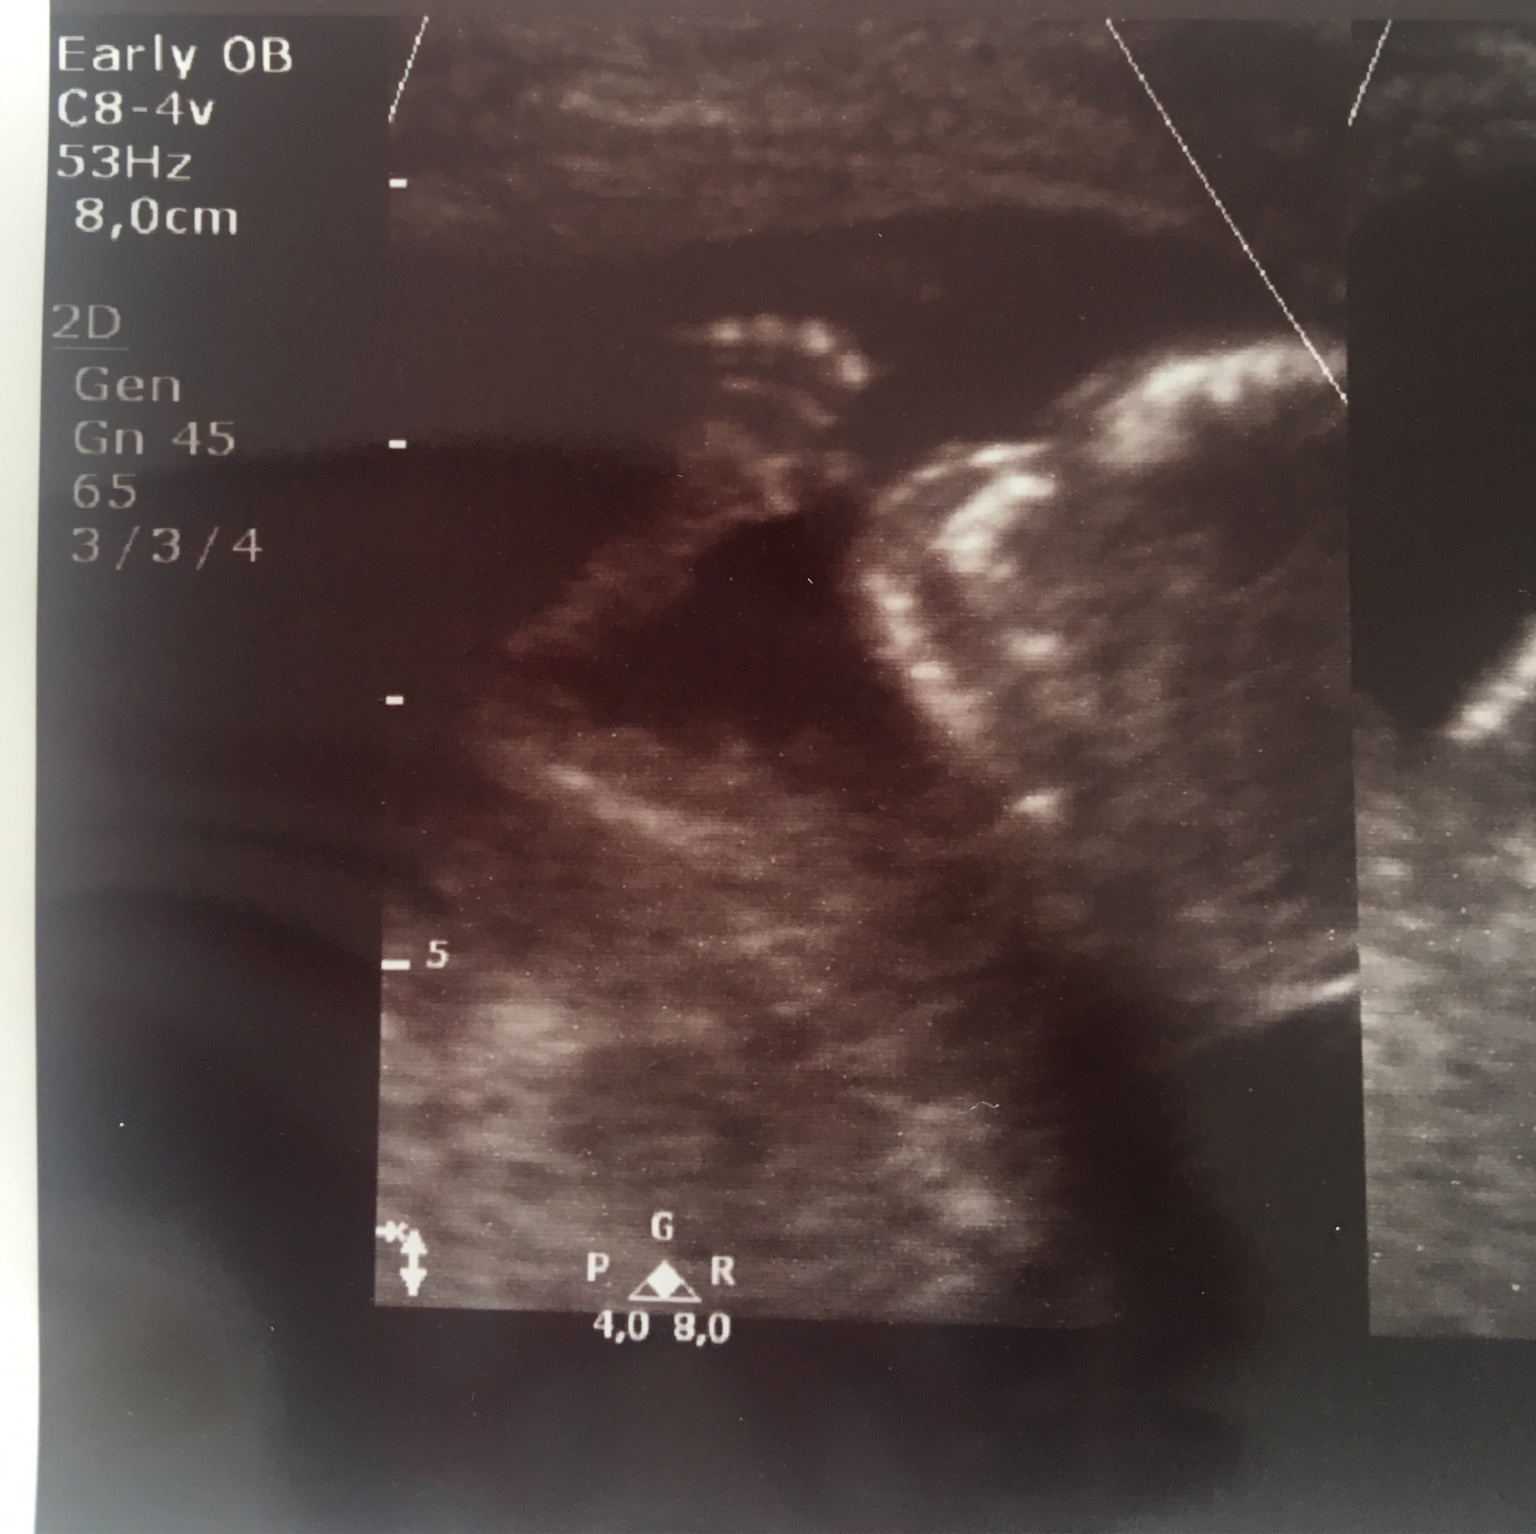

Jak zrobiłam zdjęcie to wydawało mi się że jest wyraźne [emoji12]

Edit: widzę że mocno niewyraźna jestem [emoji16] ale łapa jest [emoji23][emoji16][emoji123]